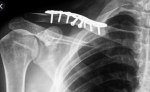

Alhamdulillah kali ini Zul berjaya bantu uruskan claim pelanggan. Claim ini dilakukan pada jun 2021. Ini adalah kes tanggalkan besi dibahu.

Pada tahun 2020 pelanggan ini mengalami kemalangan dan operation dimasukkan besi ke bahu. Kini – tanggalkan besi. Bill cecah rm11k juga. Moga beliau cepat sembuh. Amin